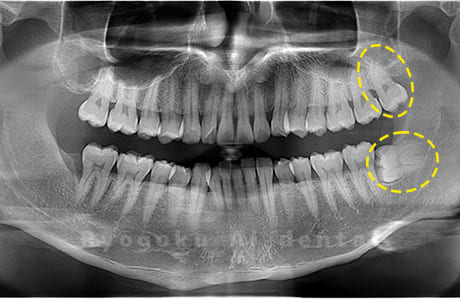

斜めに生えている親知らず

親知らずが斜めに生えて隣の歯にぶつかって圧迫してしまうタイプです。

このタイプが最も多いです。このタイプは虫歯になりやすいだけでなく、隣の歯を圧迫し、咬み合わせや歯並びに影響が出る場合もあるので抜歯をおすすめします。